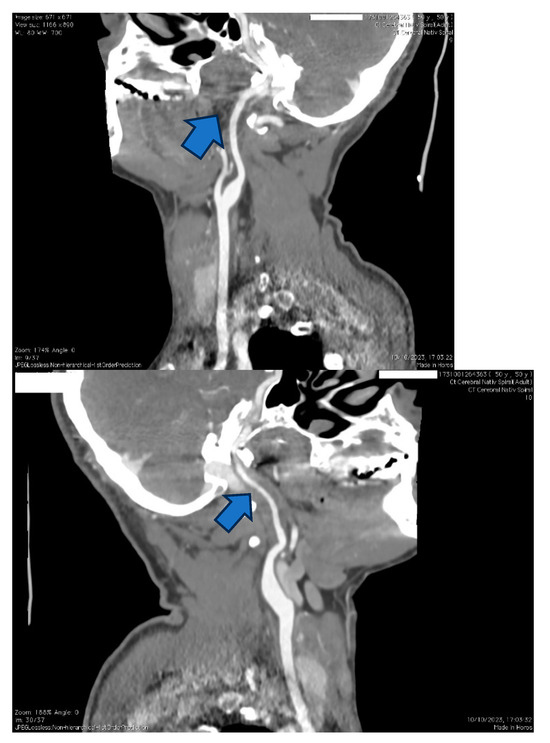

Figure 6. The same case of the 50-year-old patient, where a CTA was performed, showing focal tightening of the right carotid artery on C2 and C3 segments compared to the otherwise healthy left carotid artery.